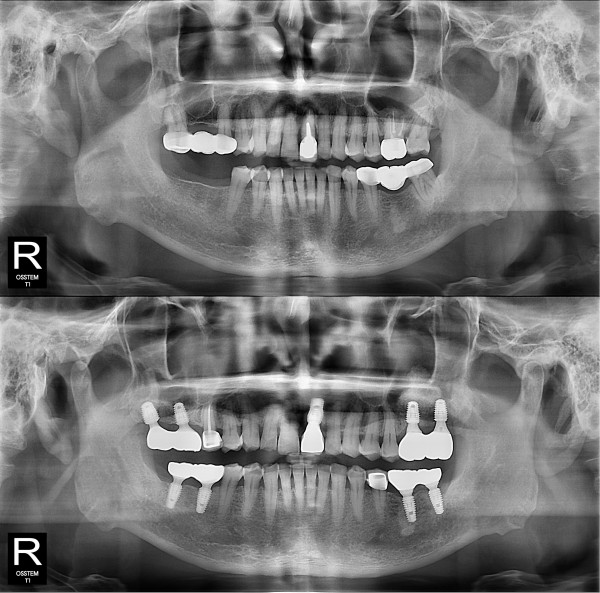

种植牙

全口种植牙